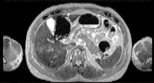

Visible Human male: Sectio transversalis 1550

CT

NMR

Pd                          / T2 \                         T1